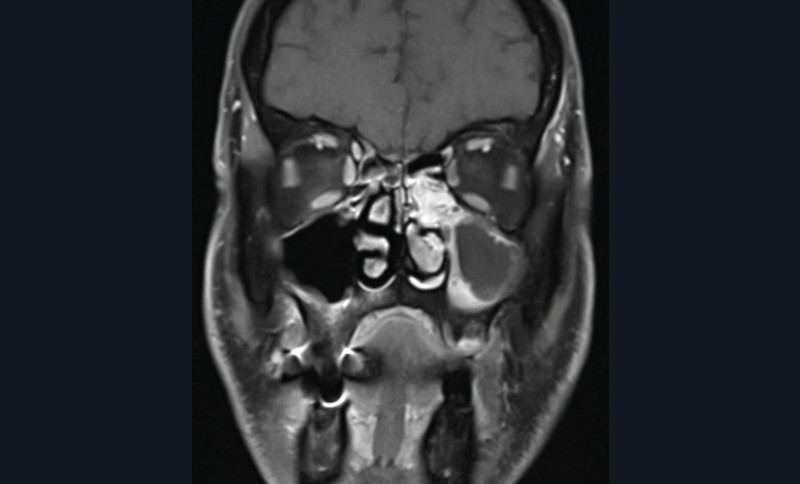

La tomodensitométrie des sinus retrouve un comblement complet unilatéral du sinus maxillaire gauche et des cellules ethmoïdales antérieures homolatérales, sans image de densité calcique intrasinusienne et sans lyse osseuse des parois (fig. 1). L’IRM montre un épaississement tissulaire de 23 mm de grand axe en regard du méat moyen gauche, avec un aspect de signal T2 hétérogène (fig. 2) et prenant le contraste en masse (fig. 3). Le comblement maxillaire gauche associé à un épaississement muqueux en cadre rehaussé correspond à une rétention en hypersignal en diffusion (fig. 4), avec diminution du coefficient apparent de diffusion (moyenne à 433 mm2/s) en faveur d’une pyocèle (fig. 5).